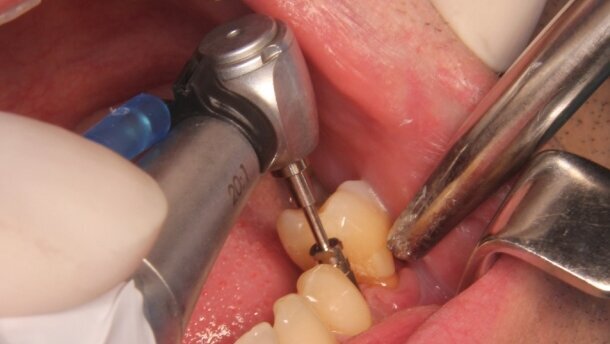

2 tygodnie od daty pierwszego zabiegu przeprowadzono próbę usunięcia złamanego fragmentu zgodnie z instrukcjami producenta (Ryc. 3):

_Wykorzystując prowadnicę F1, wprowadzono wiertło pilotowe (1000 obr./min) w celu stworzenia centralnego dołka na powierzchni odłamu, aby uniemożliwić ślizganie się kolejnych narzędzi.

_Wykorzystując prowadnicę F2, wykonano otwór w uszkodzonym fragmencie przeznaczonym do tego wiertłem (Twist drill, 2000 obr./min), (Ryc. 4).

_Z pomocą prowadnicy F3 umieszczono w wykonanym otworze gwintownik i ręczenie wykonywano naprzemiennie obroty o 1/4 zgodnie z ruchem wskazówek zegara (w celu zakleszczenia gwintu) oraz o 1/2 w przeciwnym (w celu wykręcenia fragmentu).

Wykorzystując zestaw naprawczy, z powodzeniem udało się odzyskać złamany fragment (Ryc. 5). Wnętrze implantu obficie przepłukano roztworem soli fizjologicznej i zamknięto śrubą do czasu ostatecznej osteointegracji. Zalecono wykonanie kontrolnego zdjęcia pantomograficznego (Ryc. 6). Przebieg pozabiegowy bez powikłań. Po 3 miesiącach pacjent zgłosił się w celu odsłonięcia i zaopatrzenia śrubami gojącymi wszczepionych implantów (Ryc. 7). Leczenie zostało zakończone wykonaniem i osadzeniem uzupełnień stałych w postaci koron metalowych licowanych porcelaną – przykręcanej w miejscu brakującego zęba 37 oraz cementowanej w miejscu 35 (Ryc. 8 i 9).